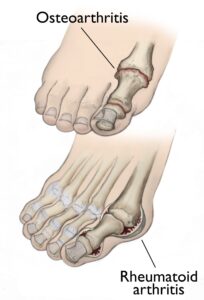

Osteoarthritis, often referred to as degenerative arthritis, is prevalent among individuals as they age, though it can also affect younger people. This condition occurs when the cartilage within a joint gradually deteriorates. Over time, the cartilage becomes rough and frayed, reducing the protective space between bones. This can lead to bone-on-bone contact and the formation of painful bone spurs, known as osteophytes. Risk factors for osteoarthritis include advancing age, obesity, and a family history of the condition. It develops slowly, typically causing increasing pain and stiffness over time.Rheumatoid Arthritis: An Autoimmune Disorder

Rheumatoid arthritis is a chronic autoimmune disease that often begins in the foot and ankle, affecting multiple joints symmetrically across the body. This means the same joint on both sides of the body is typically involved. In rheumatoid arthritis, the immune system mistakenly attacks the synovium, the protective lining of the joint. This leads to swelling and, over time, damage to cartilage, bone, ligaments, and tendons. Severe cases can result in joint deformity and disability. While the exact cause remains unknown, genetic factors likely play a role, making some individuals more susceptible to the condition. A triggering event, such as an infection or environmental factor, often activates the immune system to attack the joints, leading to the onset of the disease.

(Top) Osteoarthritis that has progressed to bone rubbing on bone and bone spurs. (Bottom) Swollen, inflamed synovium and joint deformity are signs of rheumatoid arthritis.